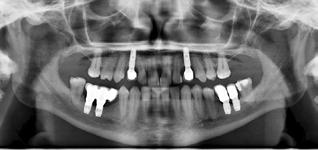

ABSTRACT

Implantatretineret protetisk rehabilitering af den atrofiske posteriore mandibel nødvendiggør ofte, at der enten foretages vertikal knoglegenopbygning før implantatindsættelse eller indsættes korte implantater ( ≤ 7 mm). Korte implantater udgør den mindst invasive behandlingsmetode, og adskillige randomiserede kontrollerede studier samt systematiske oversigtsartikler med metaanalyser har vist høj implantatoverlevelse, begrænset marginalt knogletab og få komplikationer efter op til fem års funktionel belastning. Ud fra biomekaniske betragtninger må der eksistere en nedre grænse for længden af et implantat, der kan bære en protetisk rekonstruktion posteriort i mandiblen, og en øvre grænse for, hvor høj en protetisk rekonstruktion et kort implantat kan bære (krone-implantat-ratio).

Studier med mellemlang observationstid (fem år) har imidlertid vist høj implantatoverlevelse ved implantatlængder ned til 4 mm og krone-implantatratio > 2.

I nærværende oversigtsartikel præsenteres den nuværende viden om anvendelse af korte implantater til protetisk rehabilitering af den atrofiske posteriore mandibel.

Korte implantater til protetisk rehabilitering af den atrofiske posteriore mandibel